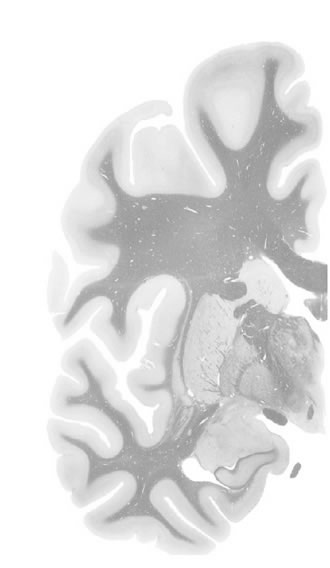

Macroscopy

5,5 mm

Slice ID: r3-1195

Plate NR: ca 26

Position: 5,5 mm